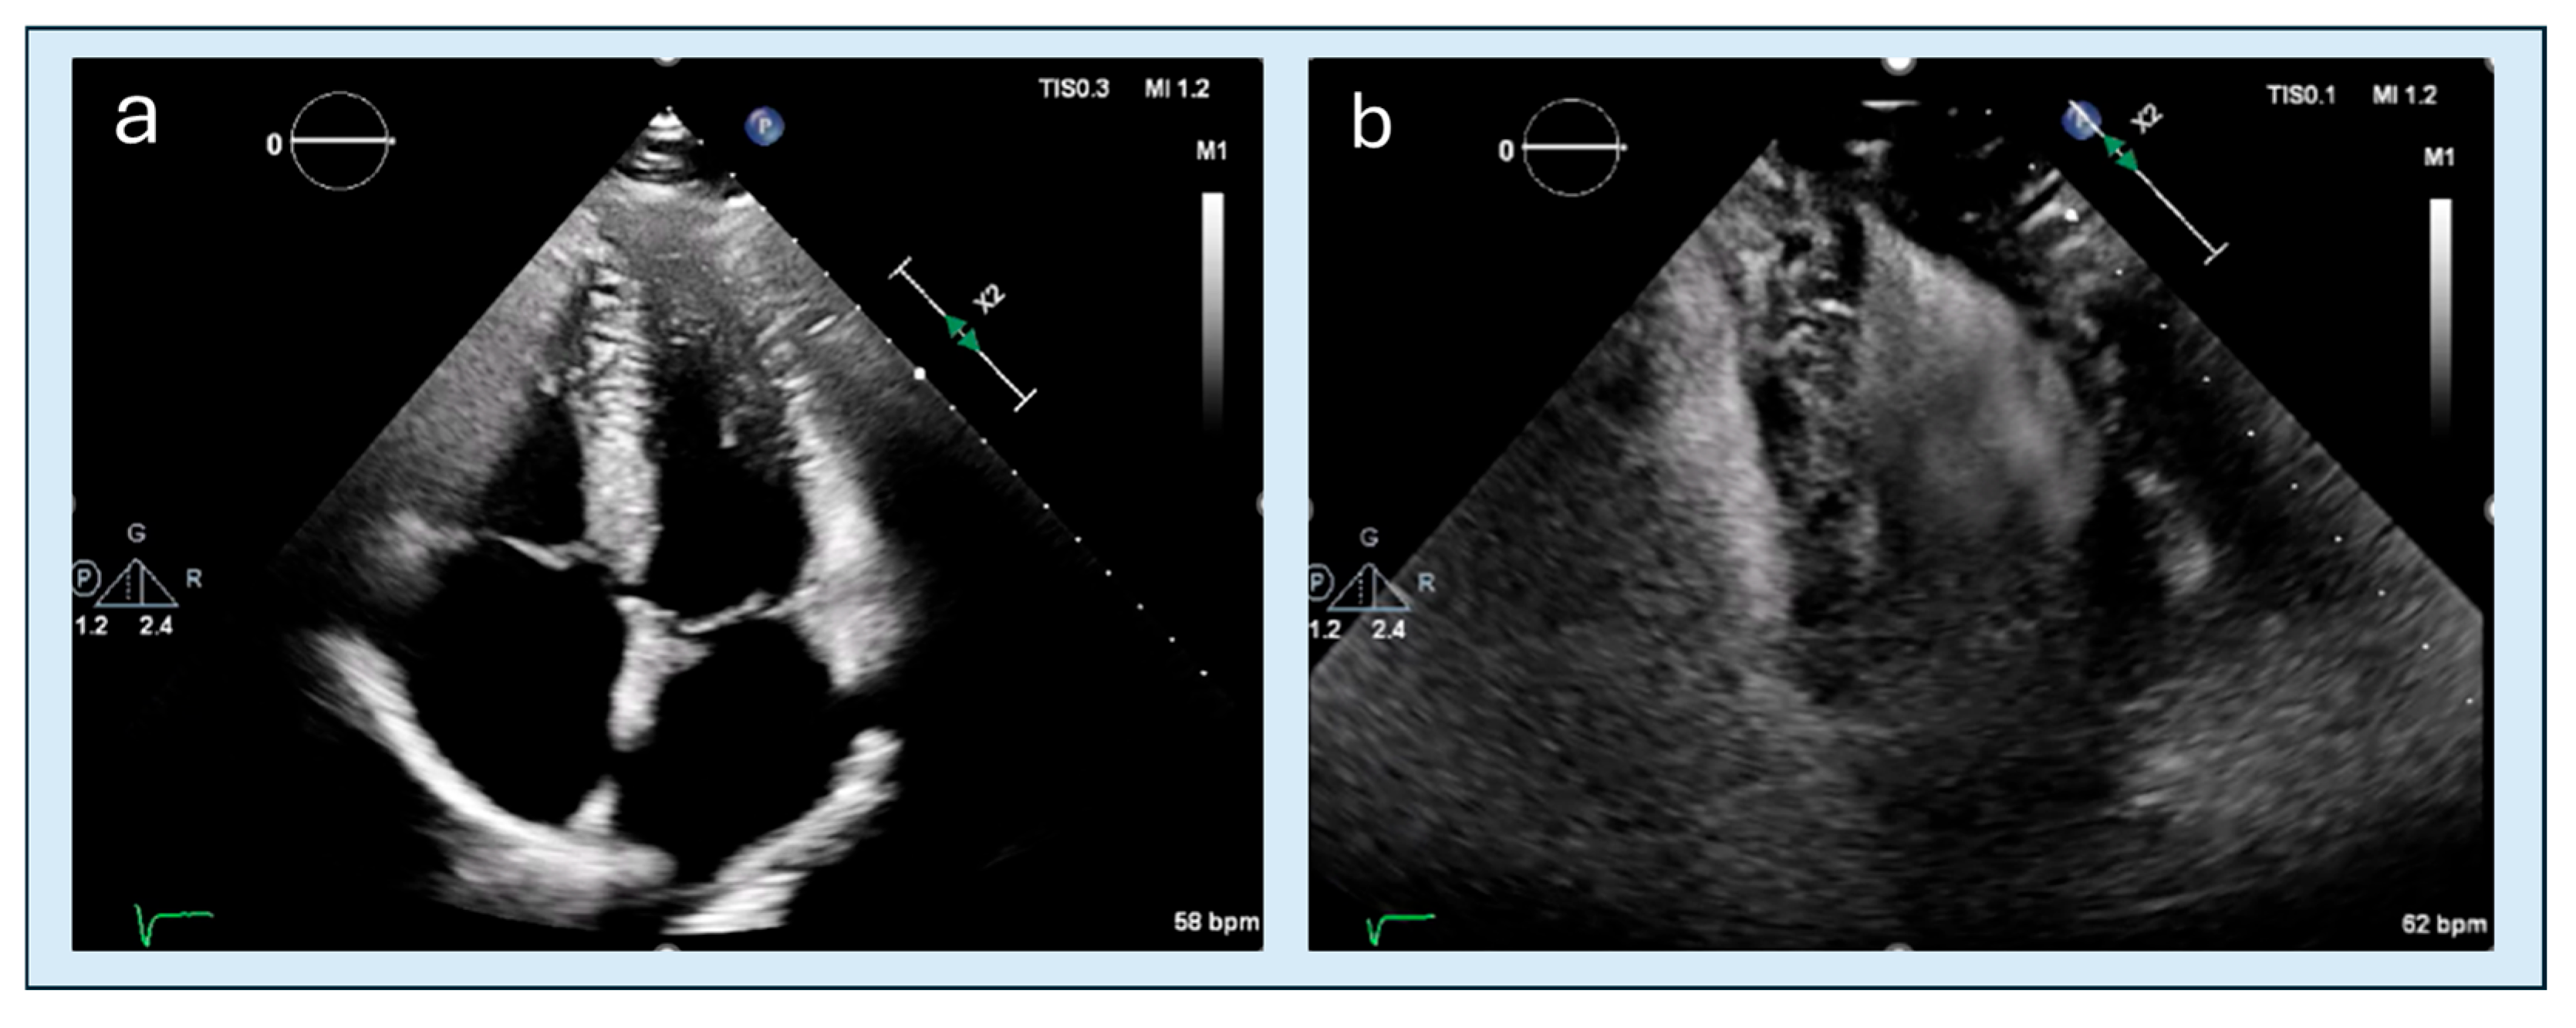

4.2. Apical Obliteration